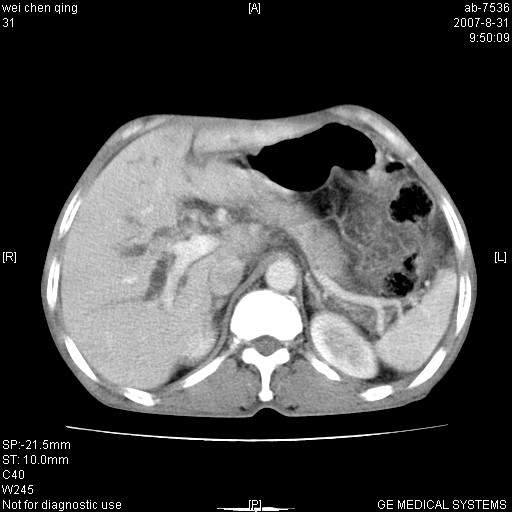

以下是引用zyyzzy在2007-8-31 14:34:00的发言:[br]该病人肝内胆管扩张,胆囊及胆总管未见明显扩张。在倒数第9层图像上可看到左右肝管结合部(肝总管)有软组织影,此处应薄层扫描。考虑肝总管占位(ca)、腹水。[br]